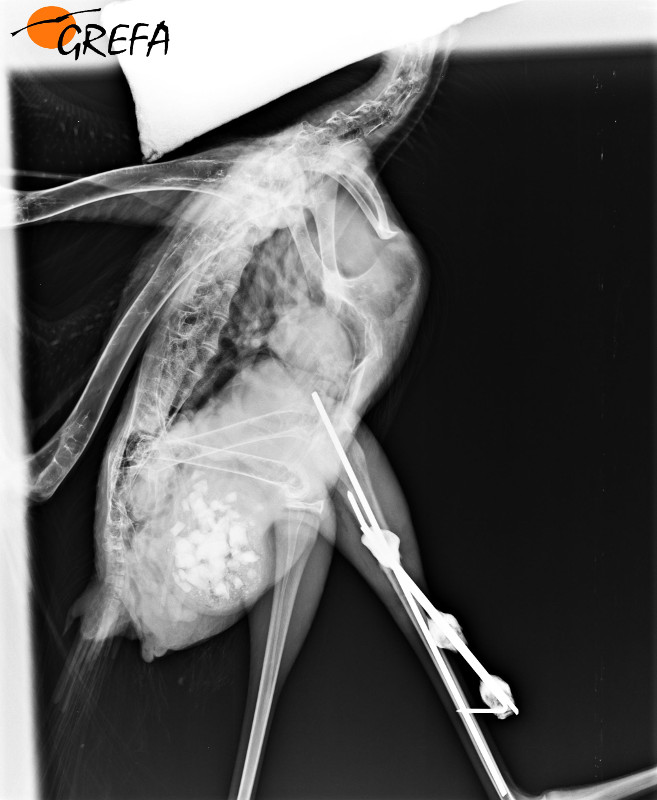

Radiografía de fijador en el tibiotarso de una cigüeña blanca.